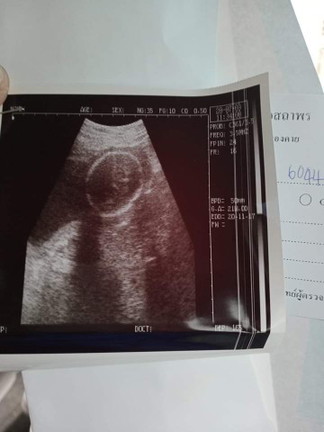

22week6วัน คุณหมอบอกผู้หญิงค่ะ คุณแม่มองไม่ออกเลย

อันนี้หัวค่ะ ถ้าดูเพศต้องดูหว่างขา